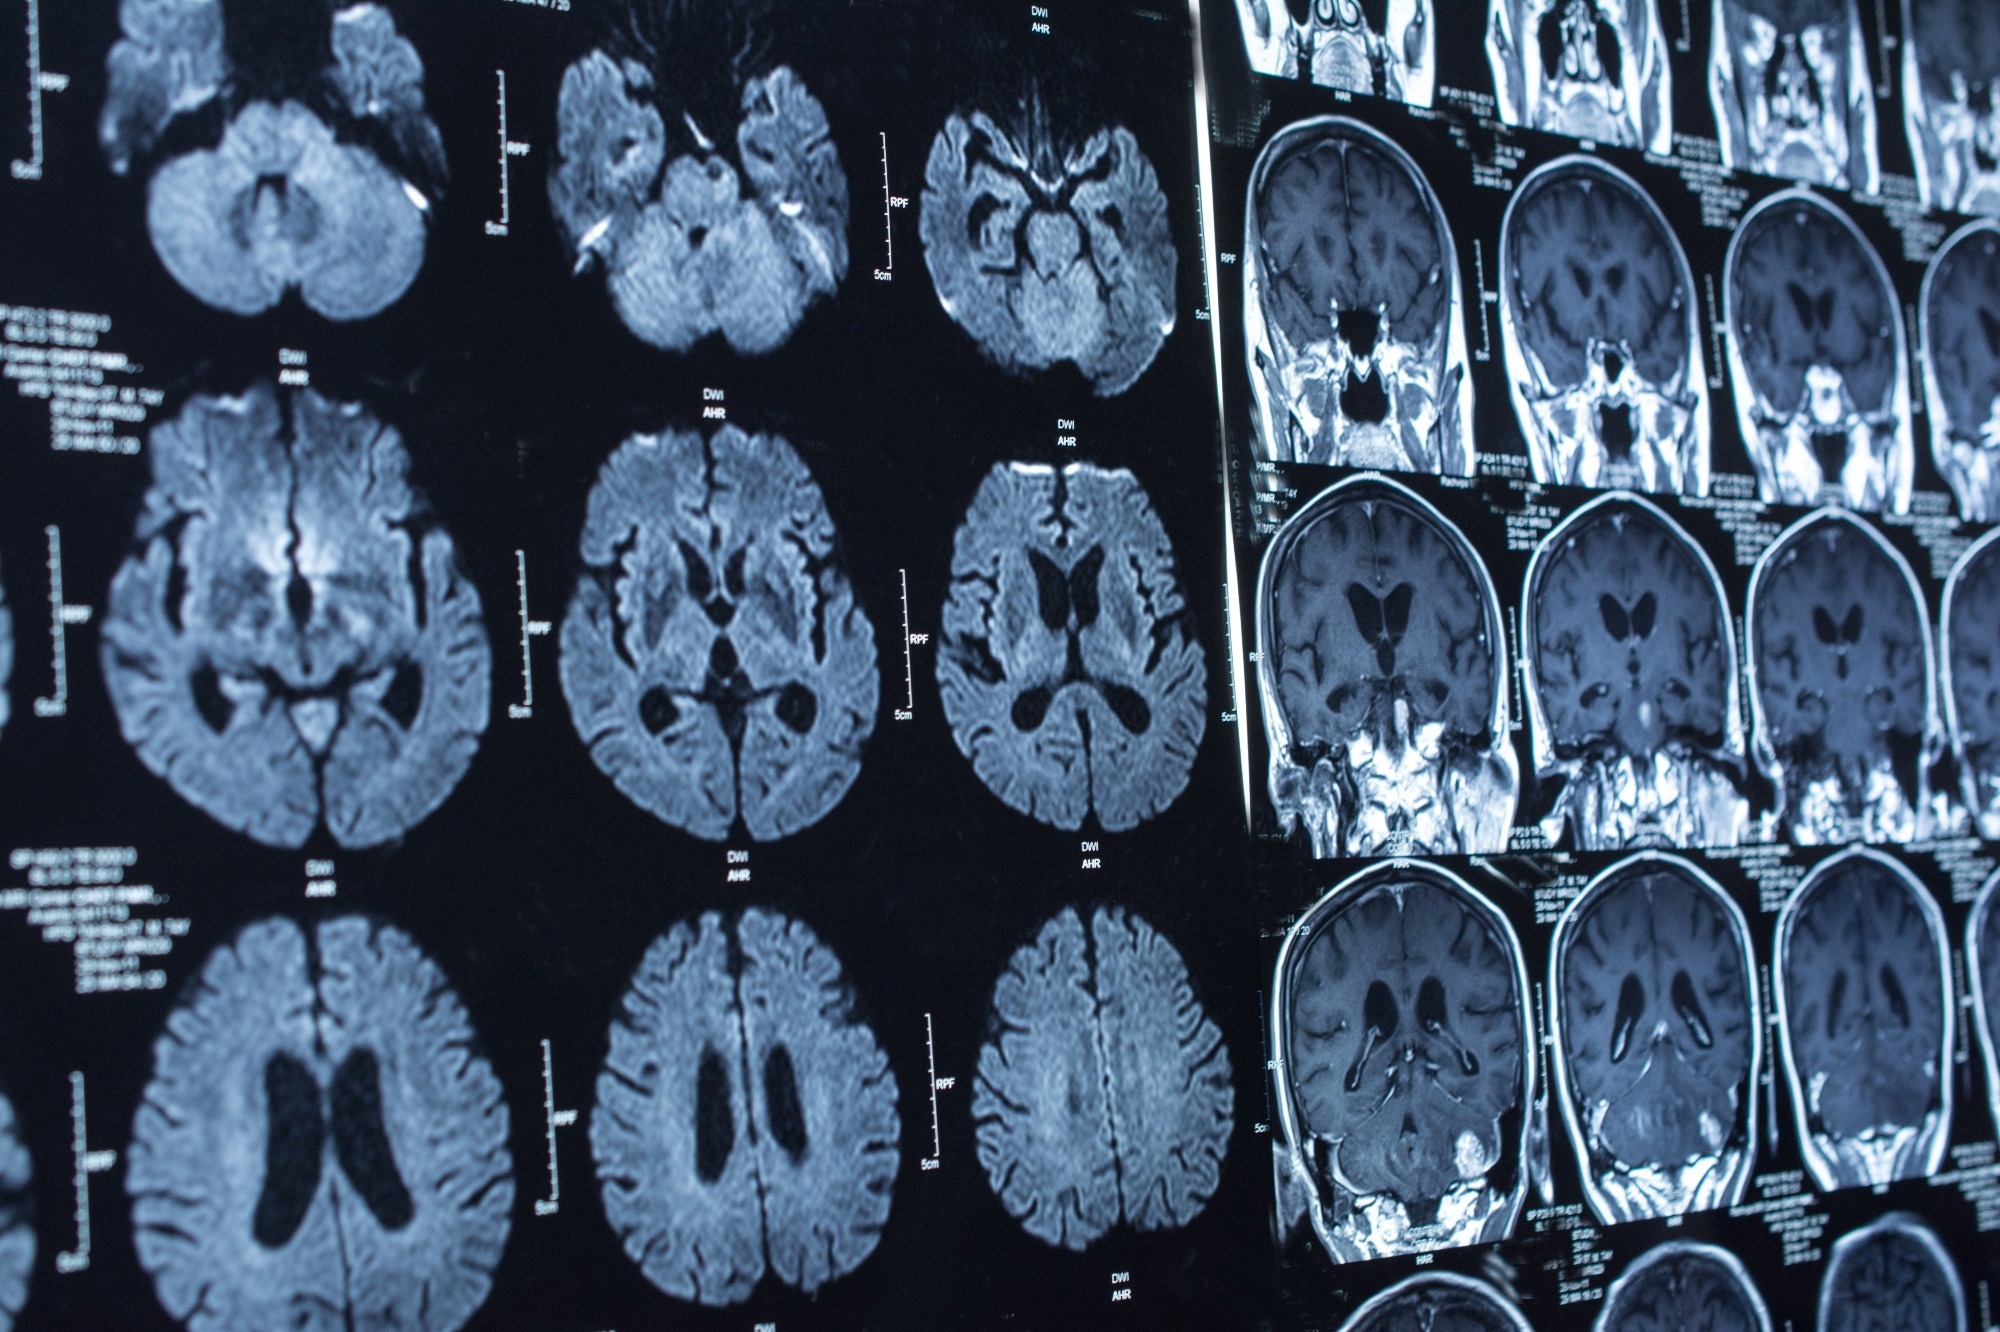

Study: Marine Plasmalogens: A Gift from the Sea with Benefits for Age-Associated Diseases. Image Credit: Tushchakorn / Shutterstock.com